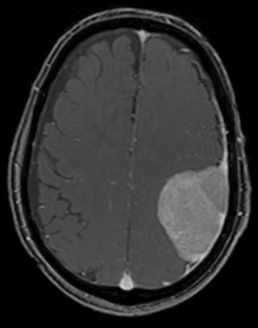

比較的に短時間で撮影できるCT検査や、より精密に調べることのできるMRI検査を行います。疑わしい場合は造影剤を使用します。画像診断は脳腫瘍の治療方針を決定するうえでも非常に重要です。診断が難しい場合や稀な脳腫瘍の場合は生検術(組織採取)を行って病理検査で診断をつけることもあります。

造影MRI検査

① 髄膜から発生する腫瘍(髄膜腫)を認める